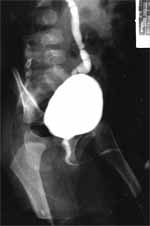

Ecografia renal: riñón derecho disminuido de tamaño, con dilatación ureteral sin hidronefrosis. Gamagrafía con DMSA: riñón derecho hipotrófico, con un área de retracción en el tercio medio y un aporte diferencial del 7%, riñón izquierdo normal con aporte del 93%. Cistouretrografía miccional: reflujo vesicoureteral grado III izquierdo.

Figura 3. Cistografía |